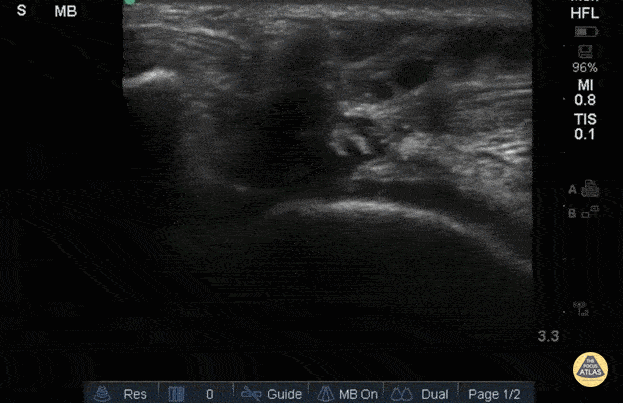

56yo M with right knee swelling after getting foot stuck under a pallet and falling backwards, found to have patella alta and right patellar tendon rupture. Longitudinal image using linear 13-6MHz probe along proximal (left) and distal (right) patellar tendon with hypoechoic fluid at site of tendon rupture. Dynamic ultrasound is useful in diagnosing tendon ruptures as the site and extent of rupture can be easily visualized, which facilitates triage to surgery, if indicated. Dr. Jasmin Harounian